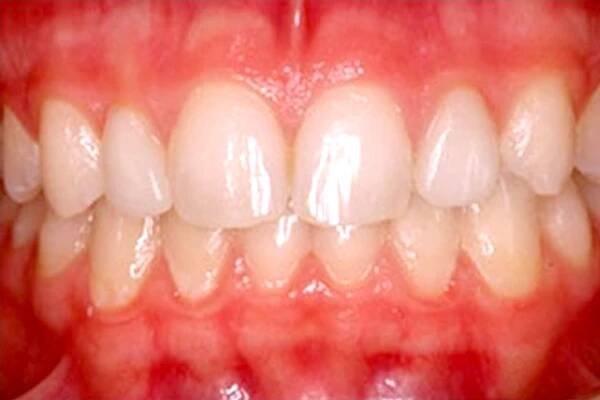

Seeing is Believing - Amazing KöR Whitening Results